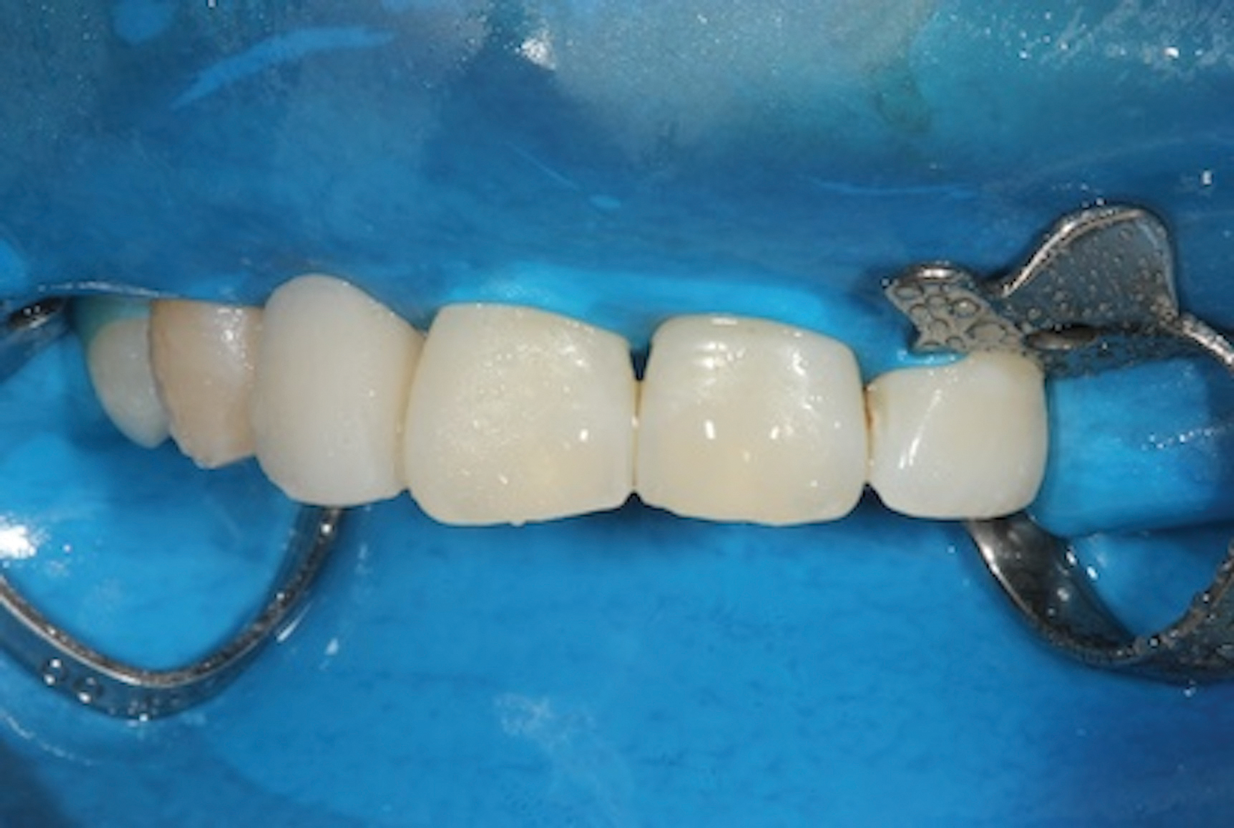

2. Precut the Fiber

The fiber-reinforced composite bridge framework design presented here is comprised of a horizontal main fiber spanning the edentulous site to create the bridge scaffold and a vertical reinforcing fiber to support the pontic. The benefit of adding the vertical reinforcing fiber to the bridge framework is that it effectively halts crack development and propagation within the composite under loading conditions. To ensure that the length of the fiber is precise, premeasure the required length in the mouth using a piece of retraction cord. Extending the measuring cord for the horizontal fiber two-thirds of the way across the occlusal surfaces of the abutment teeth will permit sufficient area for bonding and facilitate enhanced fiber stability (Figure 4). Next, place the premeasured cord onto the packaged fiber reinforcement material (Figure 5), mark the length on the package, and cut, leaving the fiber inside the package. Follow this same procedure to cut a smaller portion for the vertical reinforcing fiber. Keep the fibers in their packaging until they are ready for bonding.

(4.) Occlusal view of a piece of retraction cord being used to measure the appropriate length of fiber reinforcement material required to ensure maximum bond strength. Note that the fiber extends two-thirds of the way across the occlusal surfaces of the abutment teeth.

Figure 4